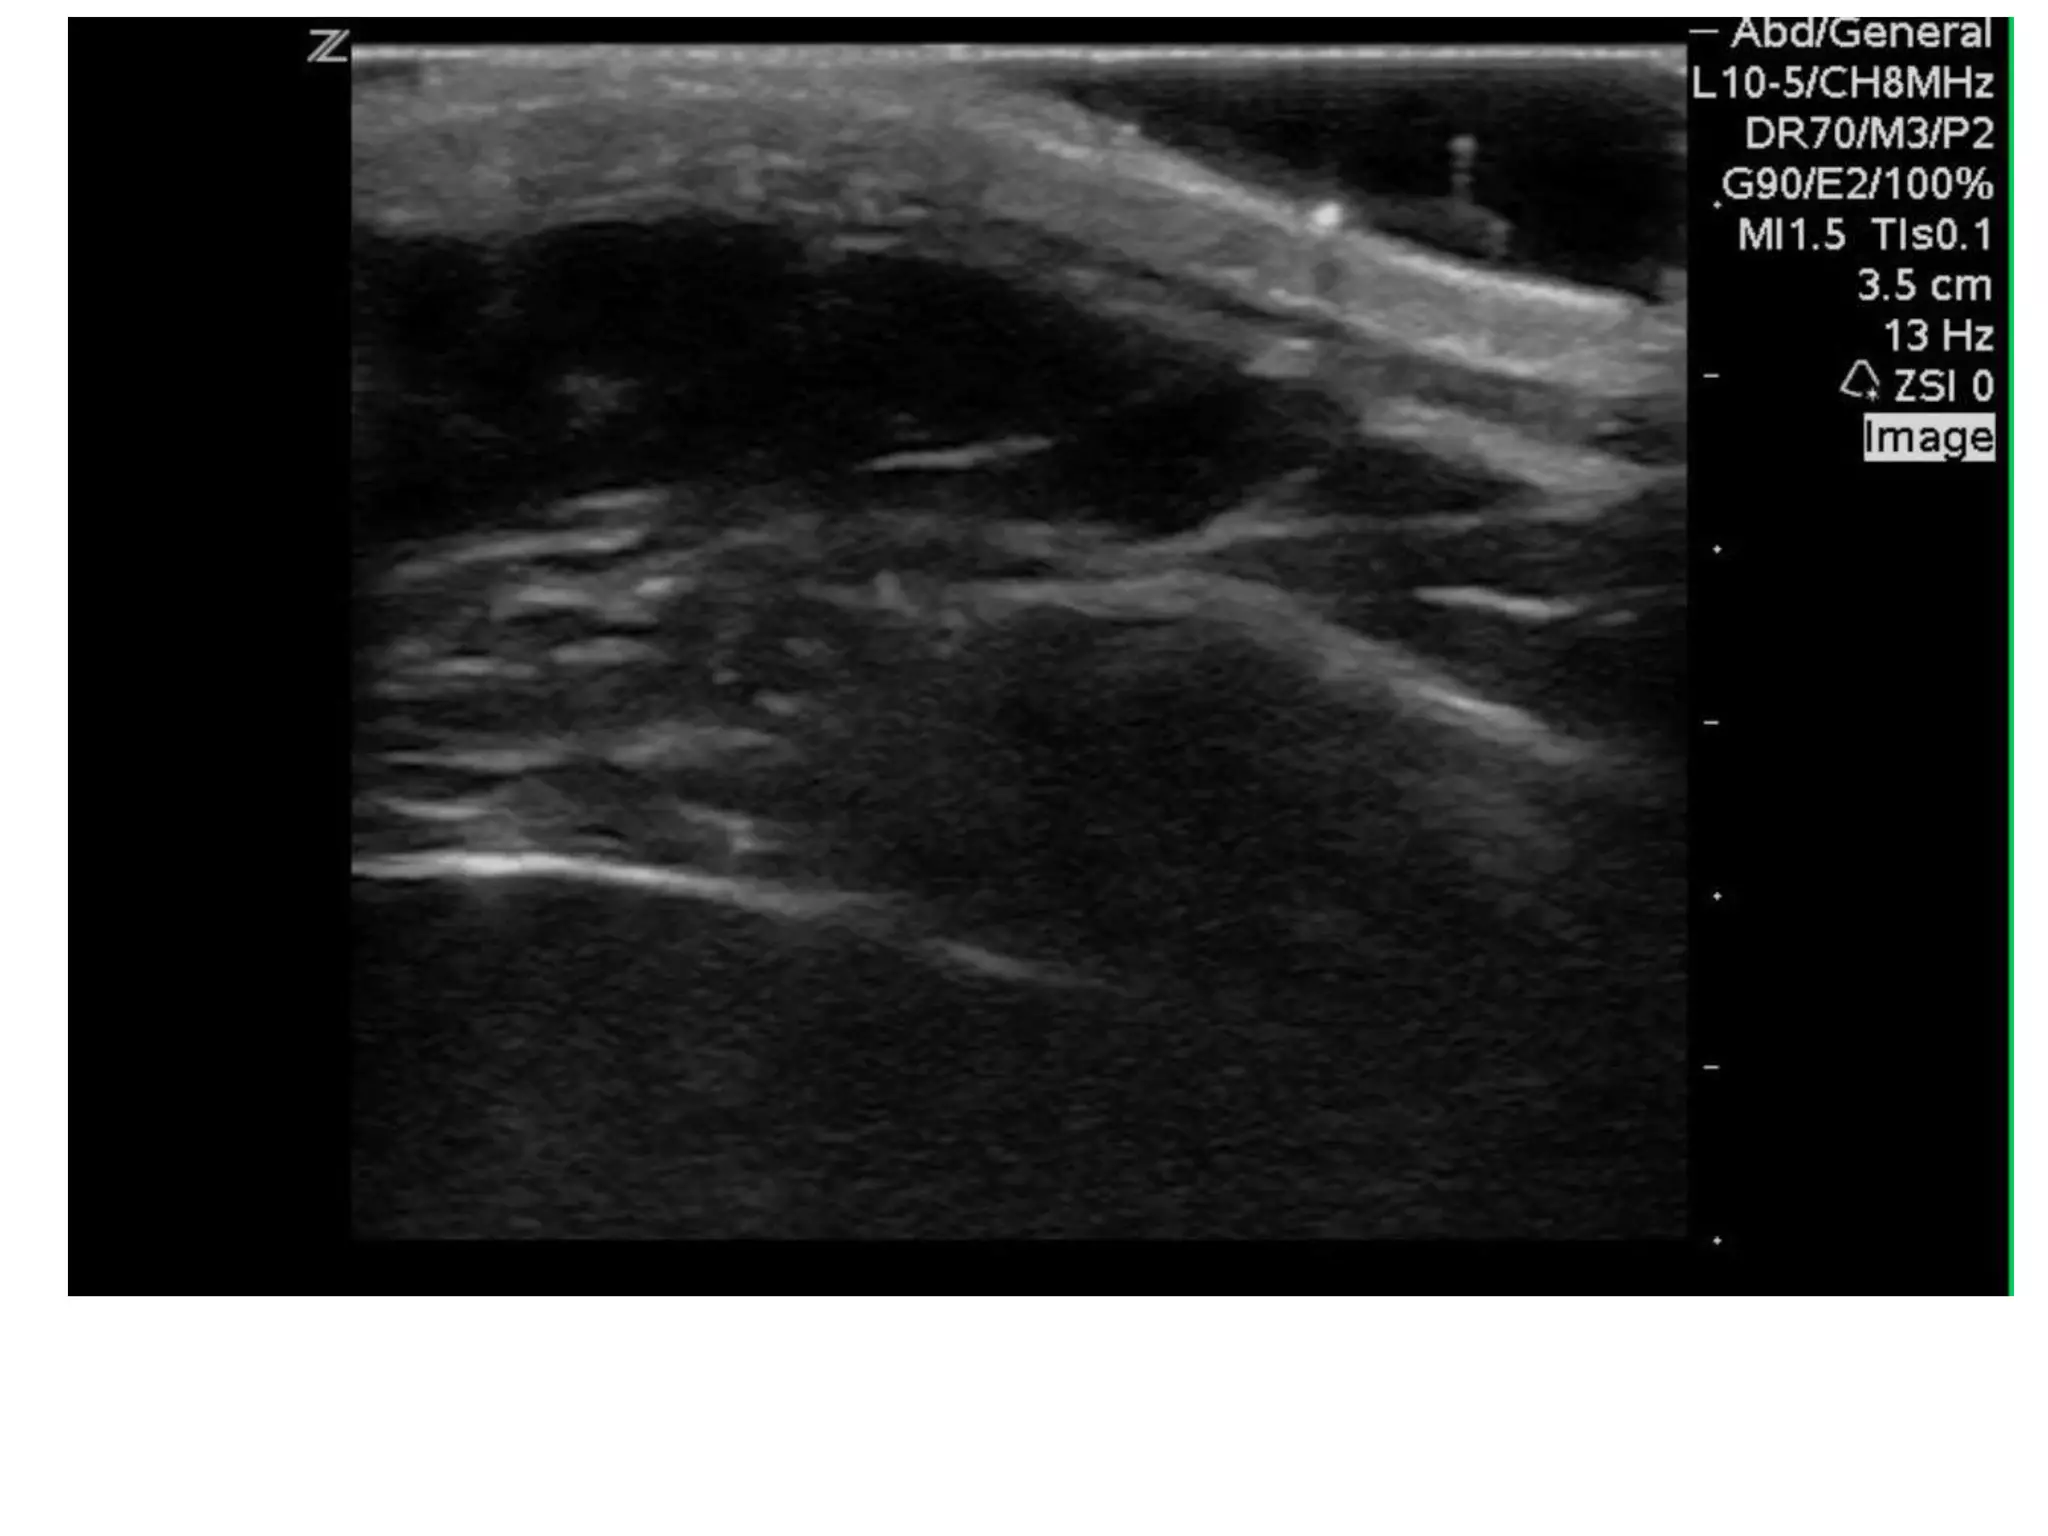

Hemothorax or Pleural Effusion

• The right pleural space  interface between the dome

of the liver and diaphragm

• echogenic curvilinear line, and echoes similar to liver

parenchyma

• Normal lung may intermittently distort this interface

during inspiration, referred to as the “curtain sign”

• anechoic or have mixed (hemorrhage, exudate,

transudate, empyema).

• Atelectatic lung can also be seen with this view

• Upright or reverse Trendelenburg positioning